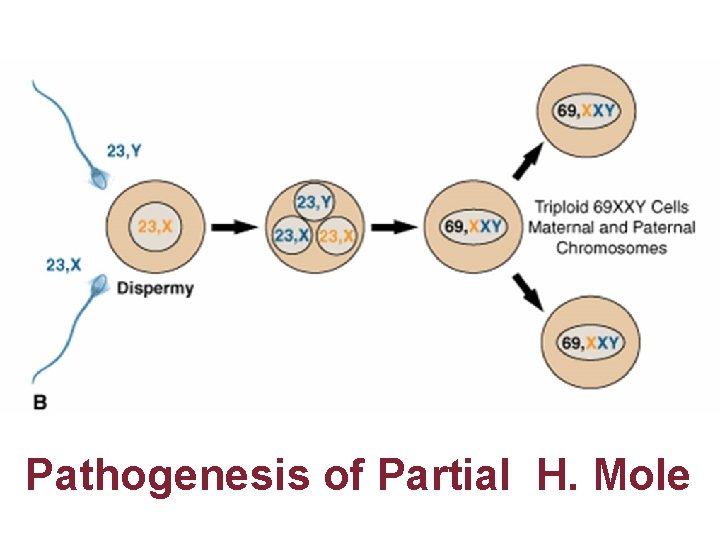

Pathogenesis of Partial H. Mole